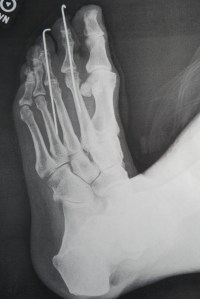

Good thing I didn’t see the x-rays before Dr. Gaggero pulled out the pins yesterday, I thought those fuckers were 2 or 3 inches long at most (a few cm), nope, deeply into my foot.

It’s deeply weird to hobble around with pins, you can never forget they’re there and how it would feel to kick something so you truly welcome the protective ‘boot’. You think of those kebab skewers growing into your toe bones.

But no, the toes said goodbye to the pins quite happily. If I’d known how long they were I wouldn’t have done weight training. No wonder it hurt more than usual.

Pins Barely Visible